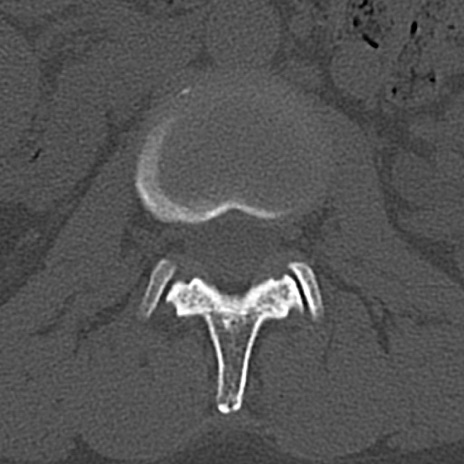

腰椎CT

横断像と矢状断像